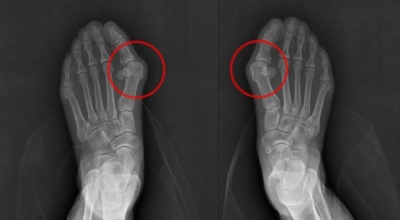

엄지발가락 통증 - 무지외반증

우리에게 잘 알려져 있는 엄지발가락 통증의 원입니다. 선천적 요인으로 인한 발병보다는 하이힐, 뾰족구두, 키높이 깔창과 같이 앞이 좁고 엄지발가락에 자극이 심한 신발 유행으로 후천성 환자가 늘어나고 있는 모습입니다. 체중 증가나 류마티스 관절염도 무지외반증의 이유가 되는 것입니다. 엄지발가락이 둘째 발가락으로 휘어지면서 대측으로 회전해서 제1중족 관절이 안쪽으로 돌출되는 무지외반증은 서있거나 걸어 다닐때 신발과 마찰해 통증과 염증이 발생해요.